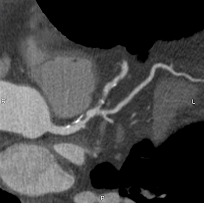

CARDIO-CT

Hightech Herz-CT kann das erhöhte Risiko eines Herzinfarktes erkennen und dabei helfen, unnötige Herzkatheteruntersuchungen zu vermeiden.

Das erhöhte Risiko eines Herzinfarktes kann durch eine präzise Herzdiagnostik frühzeitig erkannt werden.

An unserem neu erbauten Standort am Gesundheitscampus Calw bieten wir mit der Cardio-CT (Computertomographie) eine zuverlässige und schonende Methode zur Untersuchung der Herzkranzgefäße an. Dabei wird neben der Kalkmessung eine unmittelbare Darstellung der Gefäßsituation durchgeführt.

Wir führen diese Untersuchung seit ihrer klinischen Einführung Anfang der 2000er Jahre routinemäßig durch.